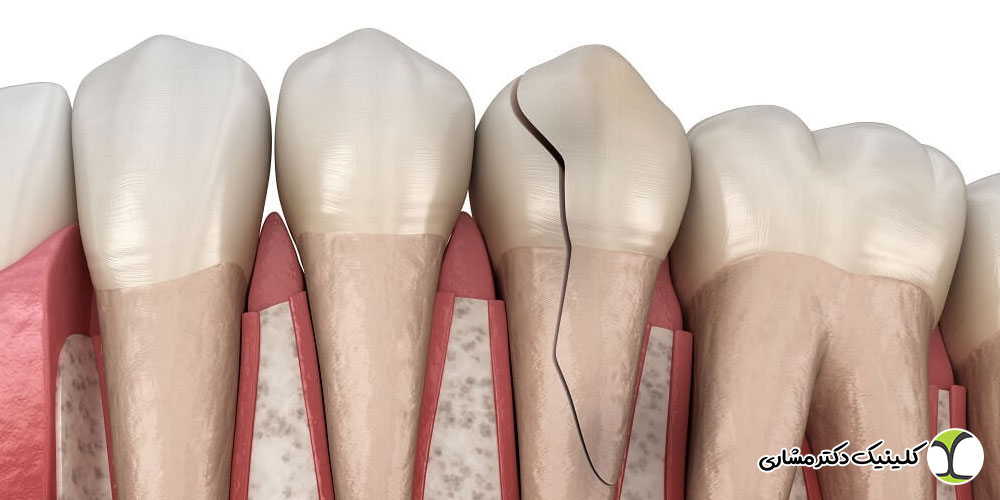

- ترک ها و پوسیدگی های قبلی: شکستگی، ترک یا پوسیدگی عمیق دندان ها ممکن است مسیر کانال را تغییر داده یا مسدود کند.